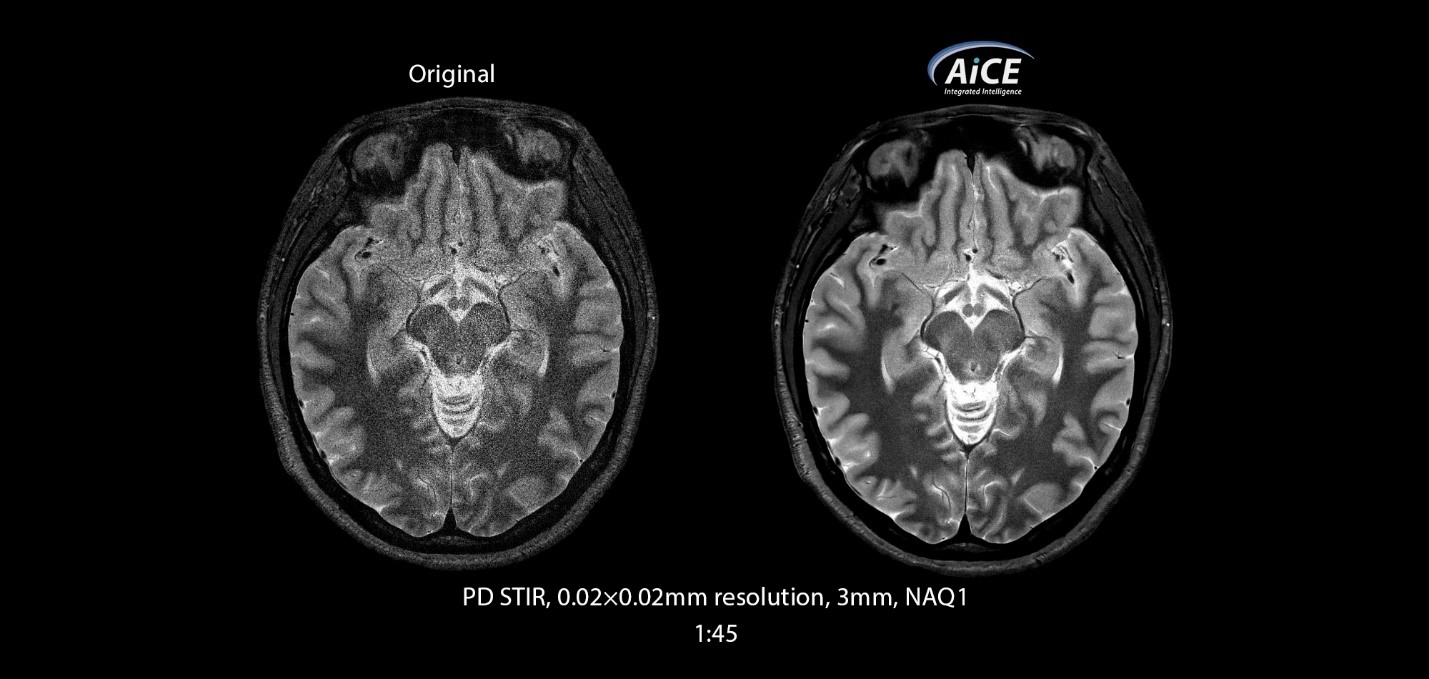

Це досягається завдяки застосуванню методу Compressed SPEEDER до послідовностей FSE, застосуванню алгоритмів штучного інтелекту AiCE, технології одночасного збудження кількох зрізів Multiband.

AiCE - чіткі зображення без шуму.

Використовуючи величезну обчислювальну потужність глибокої конволюційної нейронної ме-режі (DCNN), AiCE навчається відновленню даних на МРТ, щоб реконструювати зображення без шуму, це призводить до значного покращення якості зображення.

• Інтелектуально видаляє шум;

• Покращує значення SNR;

• Підвищує розподільчу здатність;

• Розширює анатомічну деталізацію.